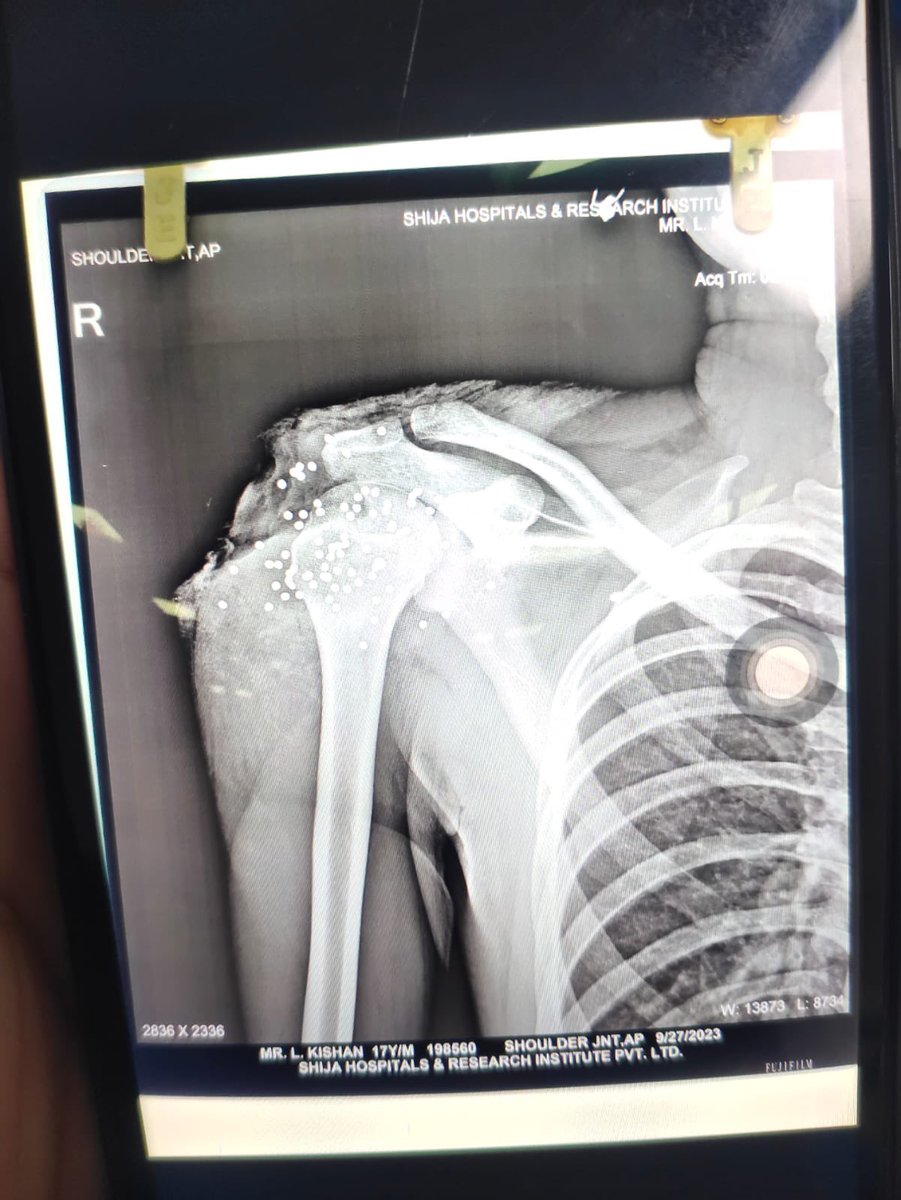

#ManipurViolence: An X-Ray of a student protester, vividly shows grievous injury to skull, shoulder torn tissue as a result from pellet gun and use of excessive force by #securityforce. News link l ukhrultimes.com/manipur-studen…